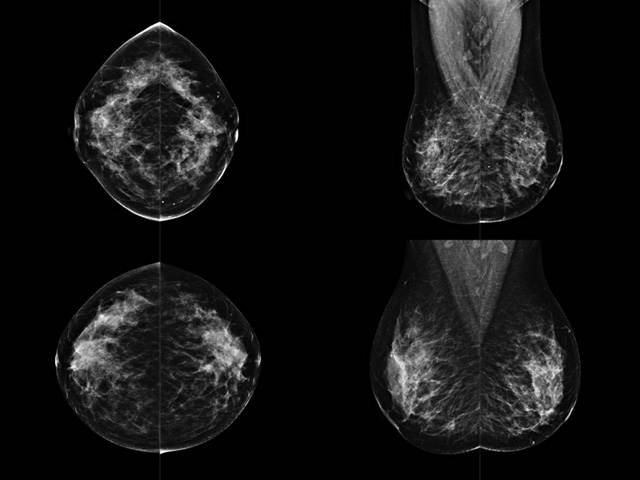

乳房檢查時(shí)候要注意一些細(xì)節(jié),需要更深入的了解這樣才能使檢查更準(zhǔn)確。乳腺DR是乳腺癌的篩查診斷工具設(shè)備。是乳房方面檢查的重要影像方法。它可以臨床檢查出早期的乳腺癌??梢耘袛嗔夹詯盒?。因?yàn)樗梢詸z查出早期的病變。對良性惡性檢查的準(zhǔn)確率達(dá)到90%以上。發(fā)病高峰年齡為45歲到54歲。50歲檢查出來乳腺癌病患,可以讓死亡率下降3成。所以30-40歲女性每年做一次乳腺DR檢查。40歲以上就一年兩次。如果家族史有乳腺癌的30歲以下也需要做檢查。清晰顯示乳腺各層組織嚴(yán)重的乳腺增生,乳腺炎,乳腺外傷也建議1年檢查一次。極大提高了早期乳腺癌的敏感度和診斷率。

大角度、高質(zhì)量的乳腺檢查,可以讓女性帶來身體健康安全。為醫(yī)生提供了高清影像數(shù)據(jù)。乳腺檢查時(shí)候各個(gè)部位影像顯示出來。白色乳腺導(dǎo)管跟纖維結(jié)締組織。模糊的是脂肪。病變一般是不透明的白色。有需要放大來檢查。乳腺DR沒有重疊偽影。輻射劑量更少。因?yàn)槿橄侔┌l(fā)病每年都有所提高,對女性都造成了嚴(yán)重的身體健康危害。早做檢查早治療是不可忽視的舉措??梢源蟠蟮慕档?/span>死亡率。保證身體健康。一般檢查避開經(jīng)期,來完7天左右是最佳的檢查時(shí)間。絕經(jīng)的女性就沒有要求。孕婦不參加乳腺DR檢查, 6個(gè)月內(nèi)準(zhǔn)備妊娠的婦女也不宜行此檢查。